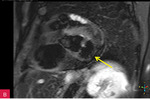

Rycina 7A-D. Obrazy rezonansu magnetycznego w osi krótkiej na wysokości pierścienia mitralnego: czarnej krwi T1-zależne TSE (A); czarnej krwi T2-zależne HASTE (B); T1-zależne echa gradientowego dynamicznie podczas podawania środka kontrastowego (C); sekwencja SSFP, pojedynczy obraz w osi krótkiej (D). W dolno-bocznej części pierścienia mitralnego od strony światła lewej komory zmiana (strzałki) niskosygnałowa we wszystkich ważeniach sygnału

W celu weryfikacji zmiany i oceny charakterystyki tkanki wykonano CMR,

w którym stwierdzono w dolno-bocznej części pierścienia mitralnego od strony światła lewej komory zmianę odpowiadającą morfologicznie CCMA, obejmującą 7,3 cm obwodu pierścienia mitralnego, o grubości w osi krótkiej do 25 mm, w osi długiej do 21 mm; zmiana ulegała brzeżnemu wzmocnieniu kontrastowemu i powodowała ograniczenie ruchomości tylnego płatka zastawki mitralnej, obejmowała struny ścięgniste mięśnia brodawkowatego tylno-przyśrodkowego. Ponadto uwidoczniono znacznie powiększone przedsionki z istotnym włóknieniem – jak w restrykcji (ryc. 7, 8).